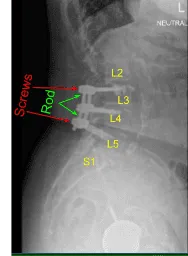

This patient had previously undergone an instrumented arthrodesis at an outside facility at L3-5. They presented with right anterior thigh and left posterior leg pain. Imaging displayed adjacent segment degeneration above and below her fusion mass which correlated well with her symptoms.